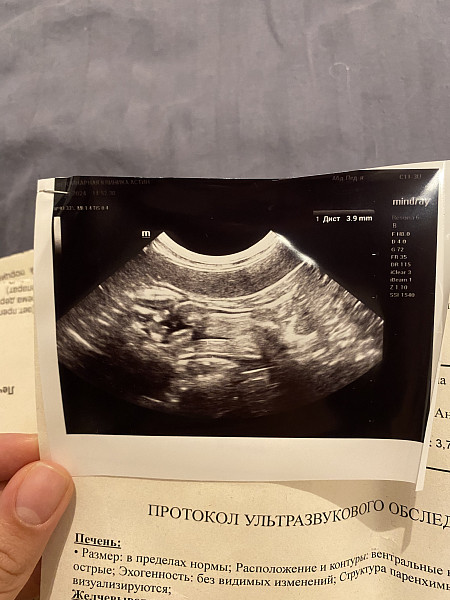

6. Дополнительно проверили на УЗИ печень, сезеленку, почки, мочевой, желудок. В двенадцатиперстной кишке обнаружено гипоэхогенное включение. Сказали ничего страшного. Фото прикрепляю